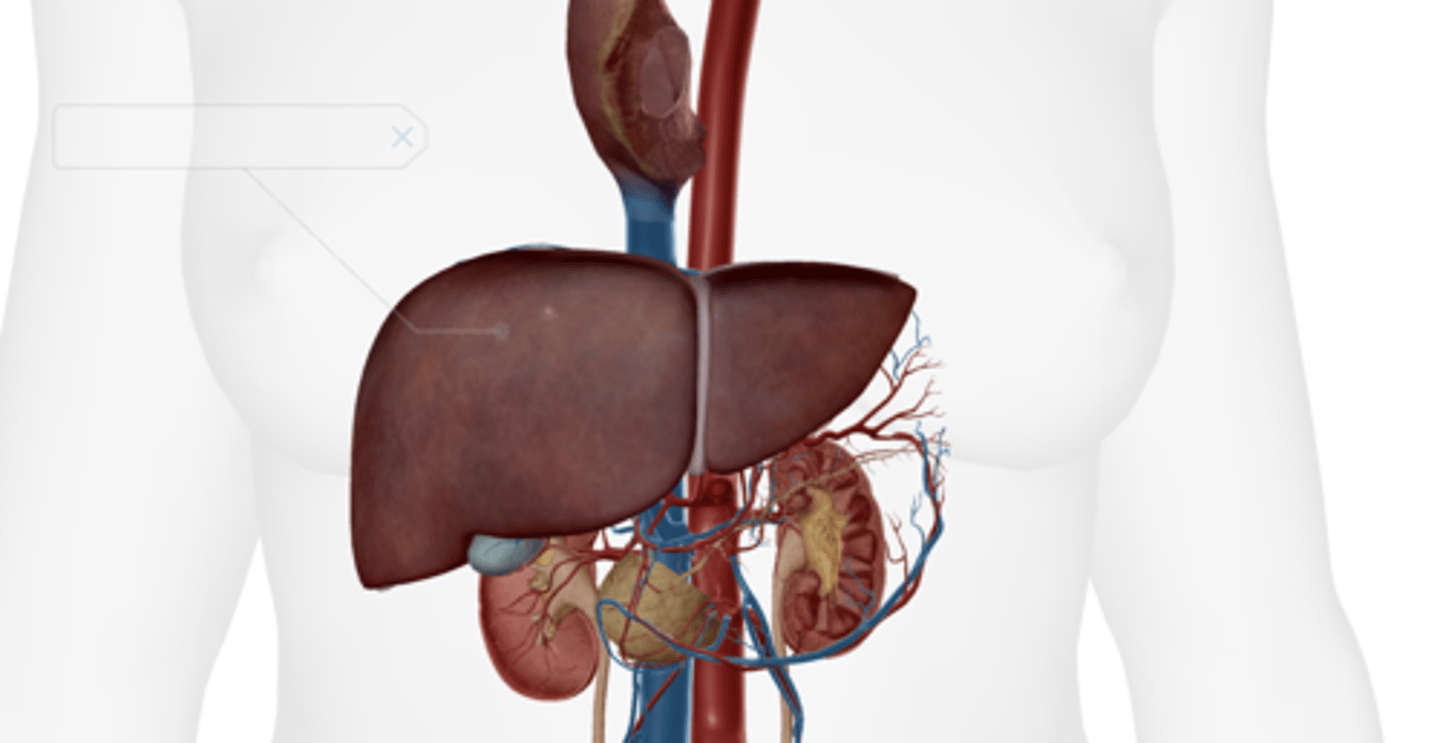

Gallbladder

Pancreas

Liver

Hepatic artery & vein